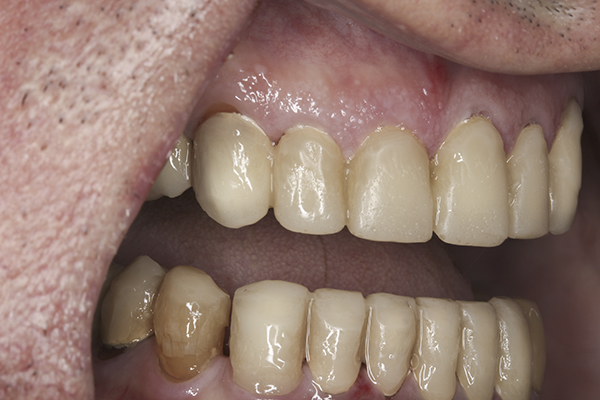

(32.) Postoperative right lateral, open view.

Figure 32